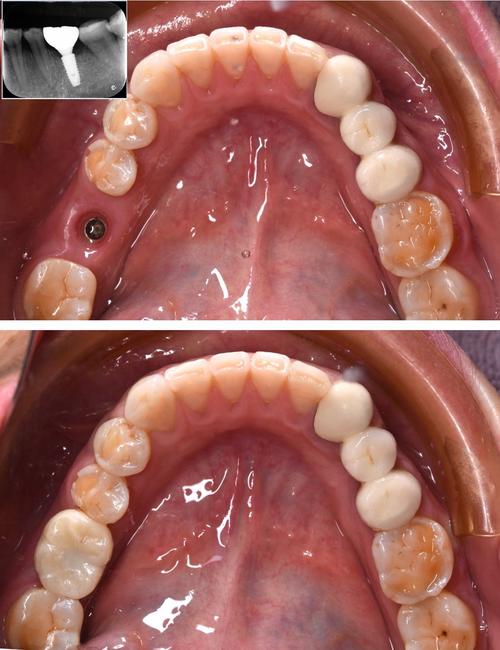

- 协禾通常配备数字化诊疗设备,如CBCT(锥形束CT,用于精准评估牙槽骨情况)、口内扫描仪(替代传统取模,更舒适精准)、3D打印技术(用于制作手术导板,提高种植精度和安全性)、种植机等,这些设备是现代精准种植的基础。

- 是否能熟练运用数字化导板技术,是衡量其种植技术水平的重要指标。